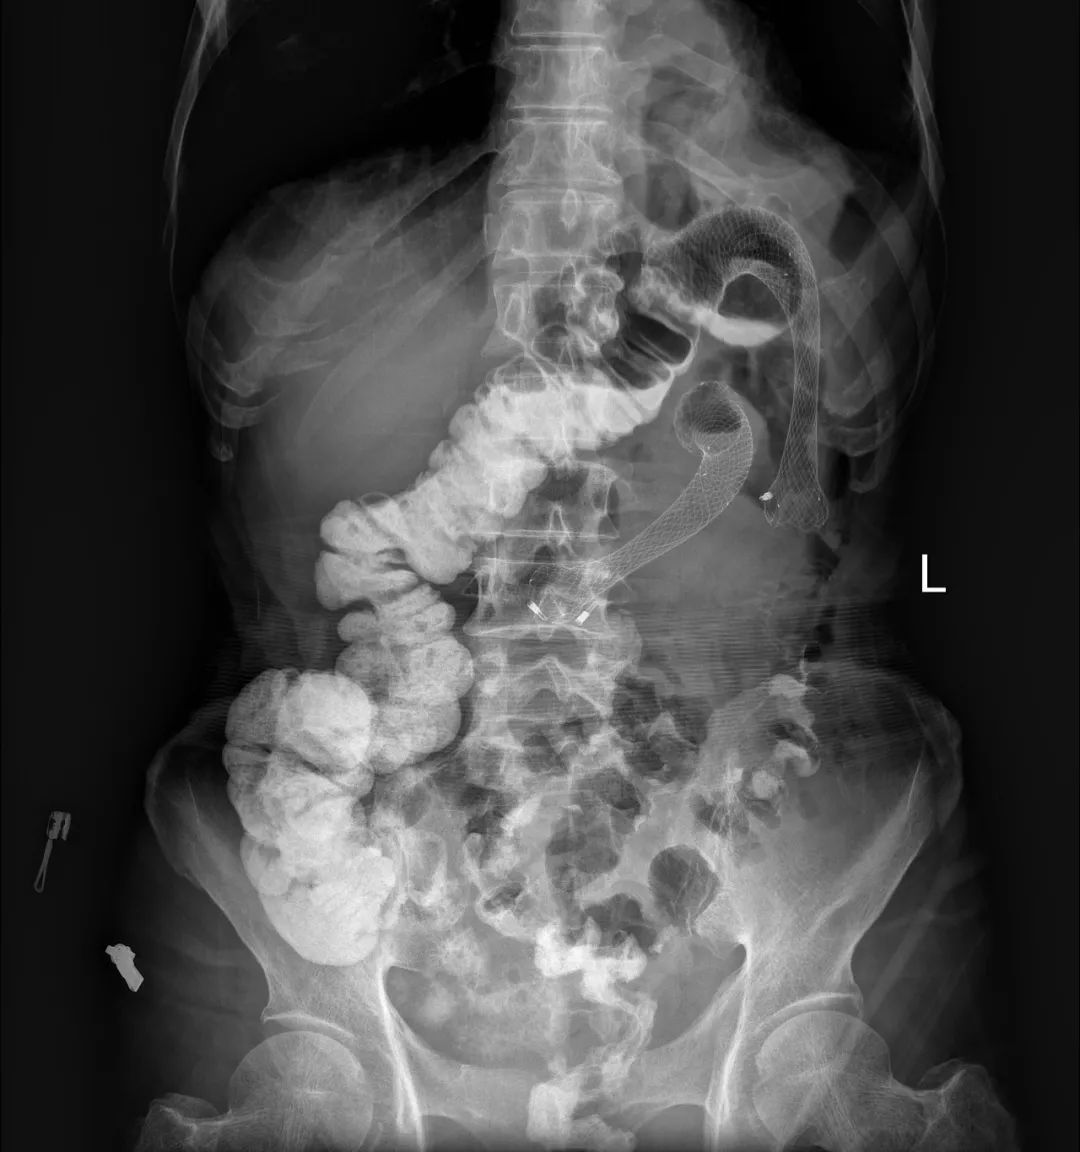

到此为止,患者已经接受了3次大的腹部手术,并接受了放化疗。但是,疾病仍然进展。2018年6月下旬患者出现恶心、呕吐,腹痛、腹胀,不能进食,X线腹部平片及腹部CT检查提示肠梗阻合并感染(见图1、图2),给予抗炎对症治疗效果差。结肠镜检查见横结肠占位伴梗阻(图3)。患者腹痛腹胀进行性加重,出现高热、血压下降等感染性休克症状。患者已经无法耐受再次开腹手术!

图1 腹部X线平片见扩张的肠管和气液平——典型的肠梗阻